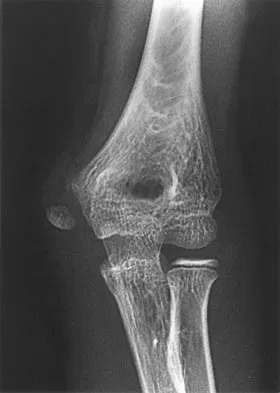

Figure 2 shows the radiograph of a 26-year-old auto mechanic who injured his right dominant elbow in a fall during a motocross race. Examination reveals pain and catching that limits his range of motion to 45 degrees of supination and 20 degrees of pronation. The interosseous space and distal radioulnar joint are stable. Management should consist of

Explanation

The radial head is an important secondary stabilizer of the elbow, helping to resist valgus forces. There has been a movement toward open reduction and internal fixation of the radial head when technically feasible, especially in a relatively high-demand athlete or laborer. The examination and radiograph suggest that displacement of the fragment is great enough to create a mechanical block. Extended splinting would only serve to encourage arthrofibrosis. Early range of motion is appropriate if there is minimal displacement of the radial head fragement, it is stable, and there is no mechanical block to motion. Fragments larger than one third of the joint surface should be excised only if it is not possible to reduce and repair the fragment. Primary excision of the radial head should be avoided if possible. Complications after excision of the radial head include muscle weakness, wrist pain, valgus elbow instability, heterotopic ossification, and arthritis. Hotchkiss RN: Displaced fractures of the radial head: Internal fixation or excision? J Am Acad Orthop Surg 1997;5:1-10.